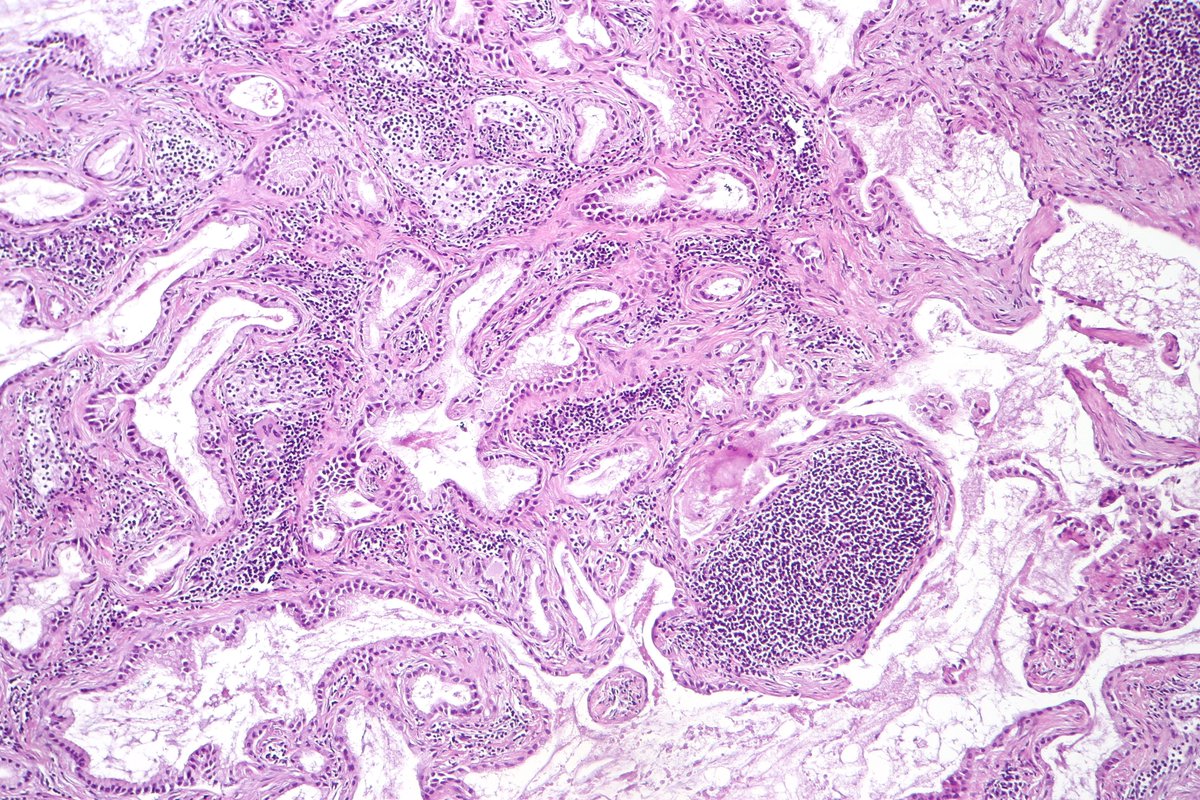

Pancreatobiliary-type adenocarcinoma lymph node metastasis showing well-formed, irregular glands associated with desmoplastic stroma. #pathology #GIPath